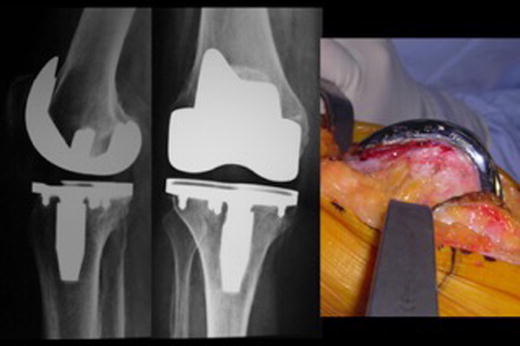

Fig. 2.

On the left, lateral and AP preoperative views of a painful stiff TKA. On the right, intraoperative sagittal femoral view showing the amount of anteriorization of the femoral component resulting in overstuffed extensor mechanism and flexion instability duo to reduced posterior femoral condylar offset

Fig. 3.

Postoperative AP and lateral view of the revision TKA which addressed the cause of TKA failure by posteriorizing the femoral component. This will simultaneously fill the flexion gap and relief the extensor mechanism